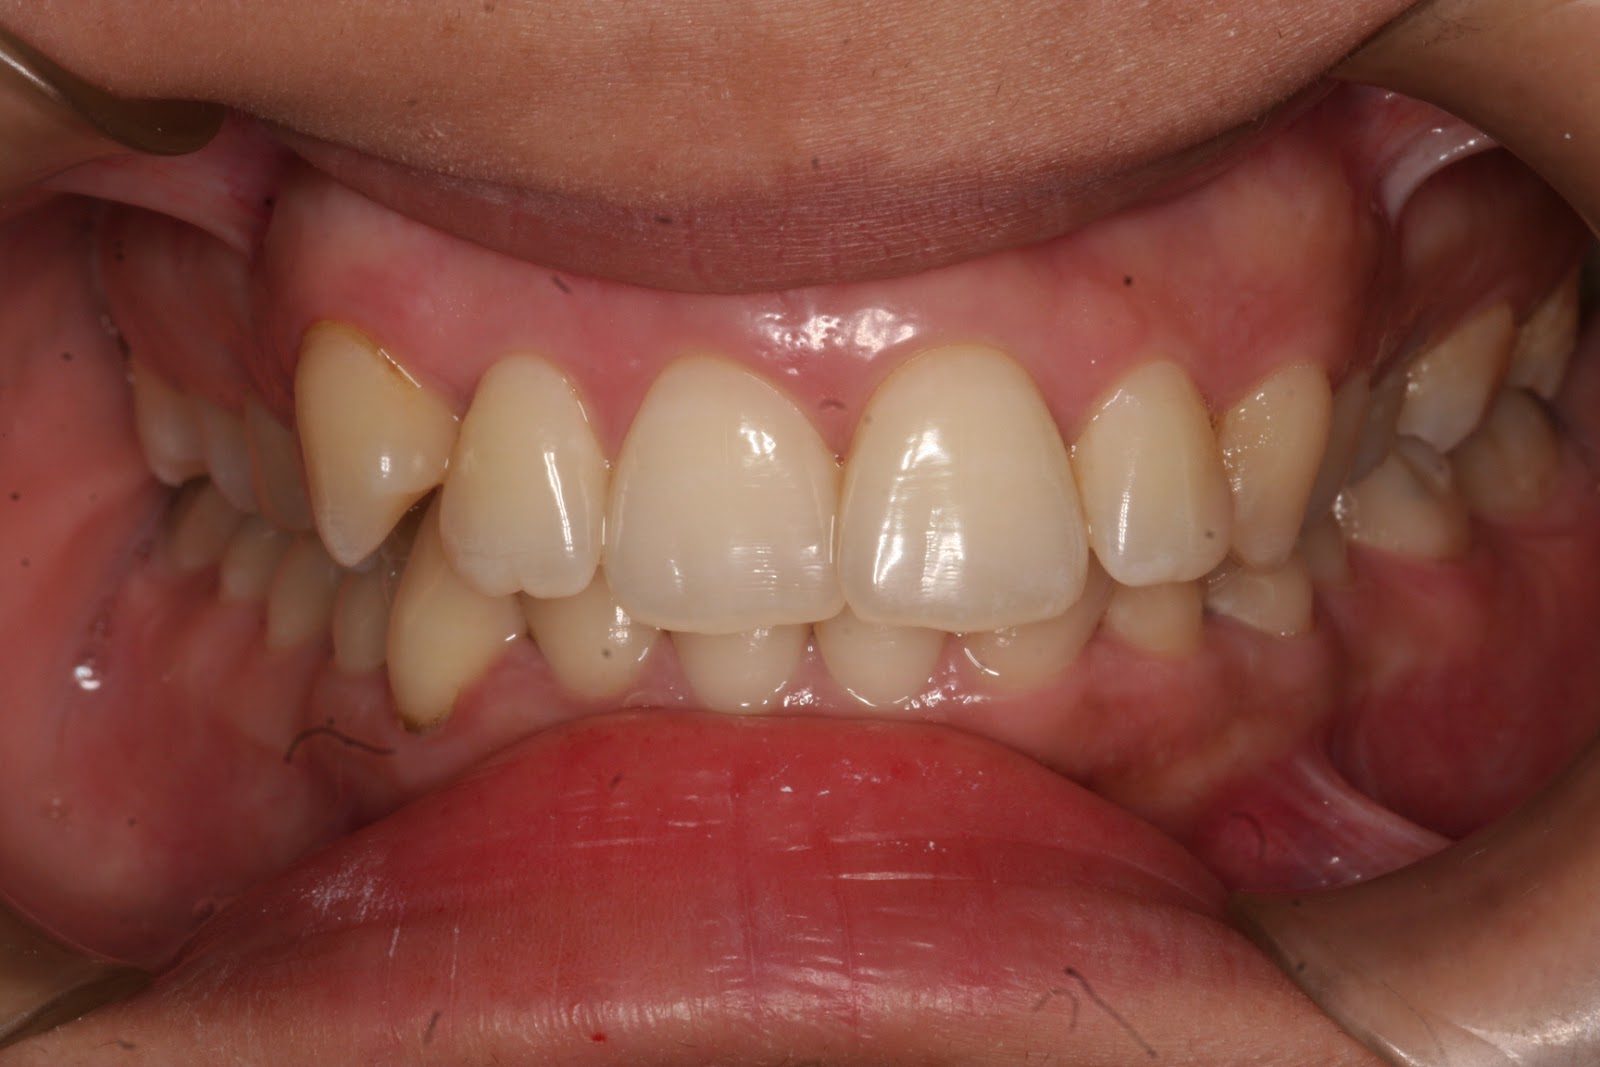

DEEP BITE (OVERBITE)

Deep

bite is excessive vertical overlap of upper and lower front teeth(normal

vertical overlap is 20—30%) and it usually associated with the jaws too close

to each other vertically, and result in excessive eruption of both upper and

lower front teeth. If deep bite left untreated, it could result in tooth wear,

fragility and shortening of front teeth, and sever deep bite trauma to gum.

Early treatment

of deep bite is faster and more stable.